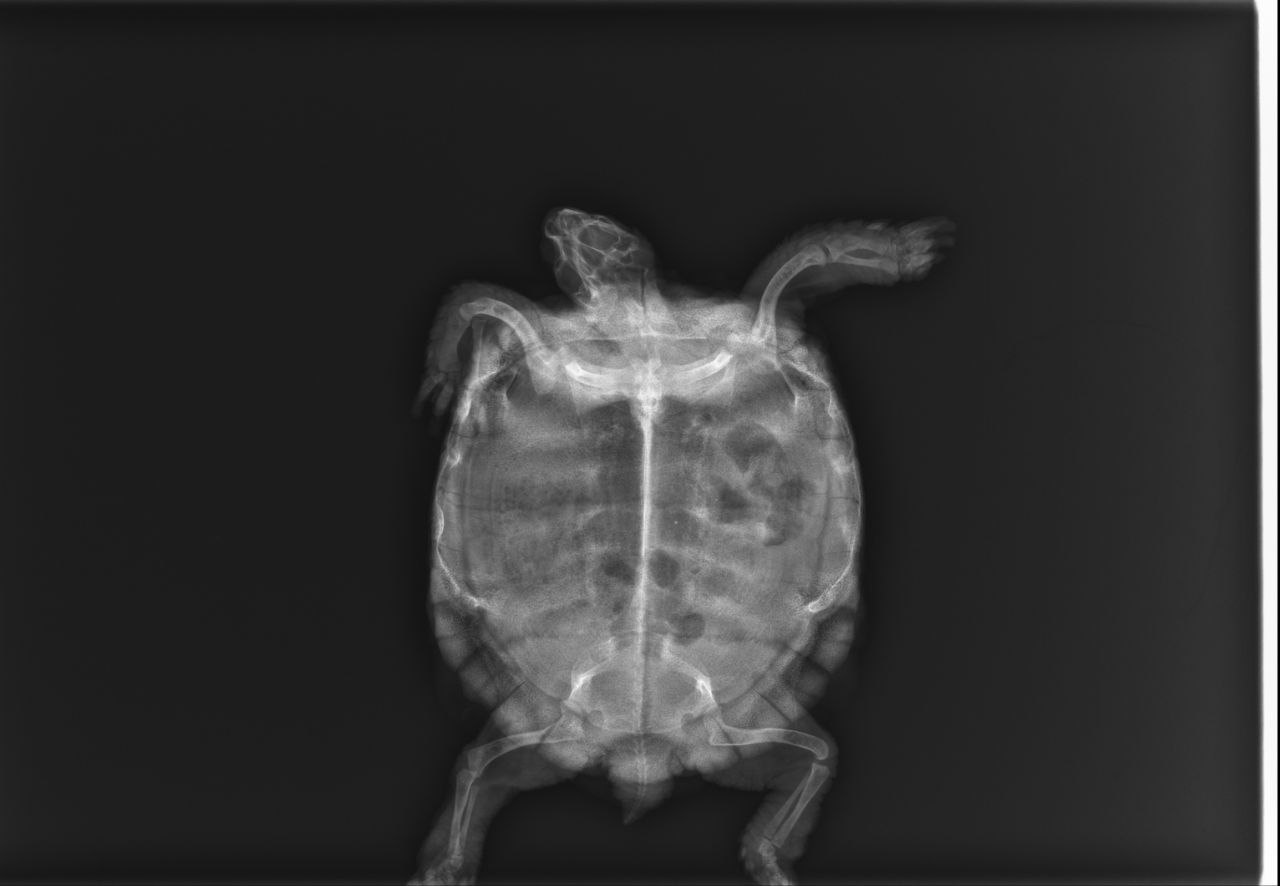

первый рентген:

pervyi-rentgen.jpg

Во-первых в такой проекции никаких лёгких не видно, но видно, что жкт был забит газами и каловыми массами.

Для того, чтобы увидеть лёгкие нужно делать другие проекции. Поэтому лечение и диагноз были неверными. Более того, такое количество фуросемида могло добить и без того больные почки, т.к. они у всех среднеазиатов в неволе слабое место, тем более, что она раньше жила под батареей.